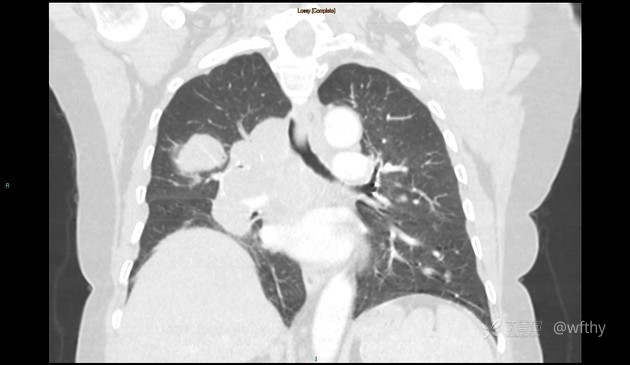

病例女65,头部肿块